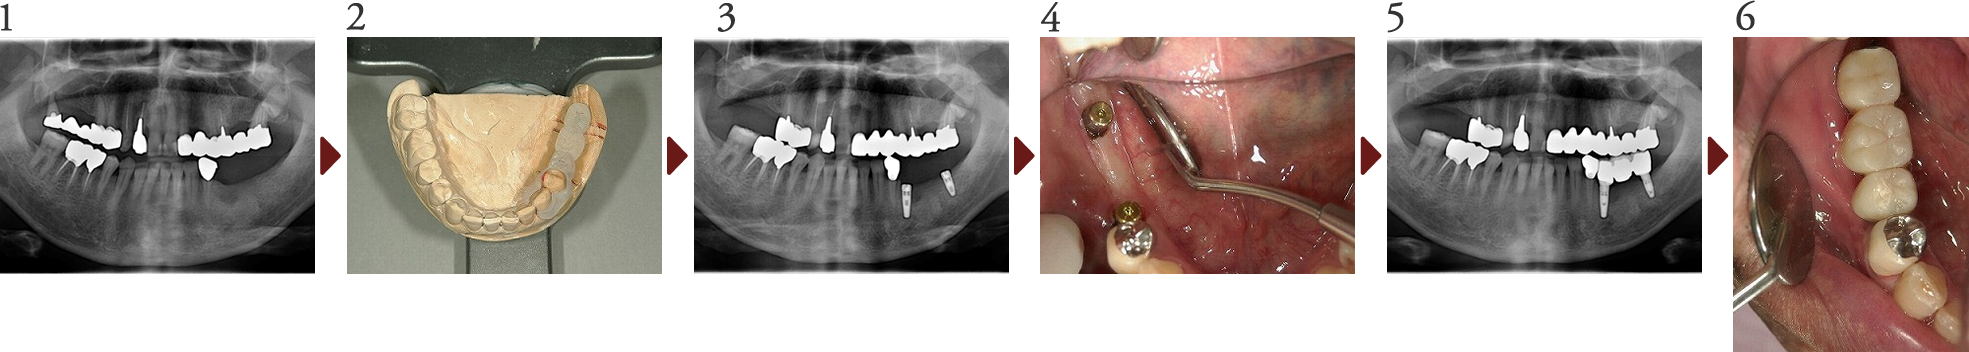

Case.7

欠損修復(インプラント修復)

患者様は全顎的処置を主訴に当院を受診されました。

下顎の欠損部分は義歯の違和感を理由にインプラントによる修復を希望されました。当院ではまず模型上で診断用のWAX UP、ランドマークシステムでCT診断を行い、インプラント埋入ポイント及び上部補綴物形態を決定していきます。

その後インプラント体の埋入、上部構造の作製へと進み、最終的にプロセラチタンアバットメントに上部補綴物を無事装着いたしました。

患者様は「義歯と違い違和感もなく、なんでもしっかり食べられます」と喜んでおられ、最後に歯科衛生士からのメインテナンス指導を熱心に聞いていました。

(技工担当:北見市デンタルプランニング 工藤 利一氏)

インプラント手術の診査診断には、シロナ社のSIDEXISとアイキャット社のLandmarkシステムを採用し、インプラントはカムログ社、インプラントダイレクト社、GC社、ノーベルバイオケア社のものを状況に応じ使用しております。 尚、保証期間はインプラントフィクスチャーは5年間、上部構造は3年間となります。